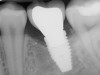

Fig 5. Bone loss shown on radiograph confirms the presence of peri-implantitis and peri-mucositis.

Figure 5